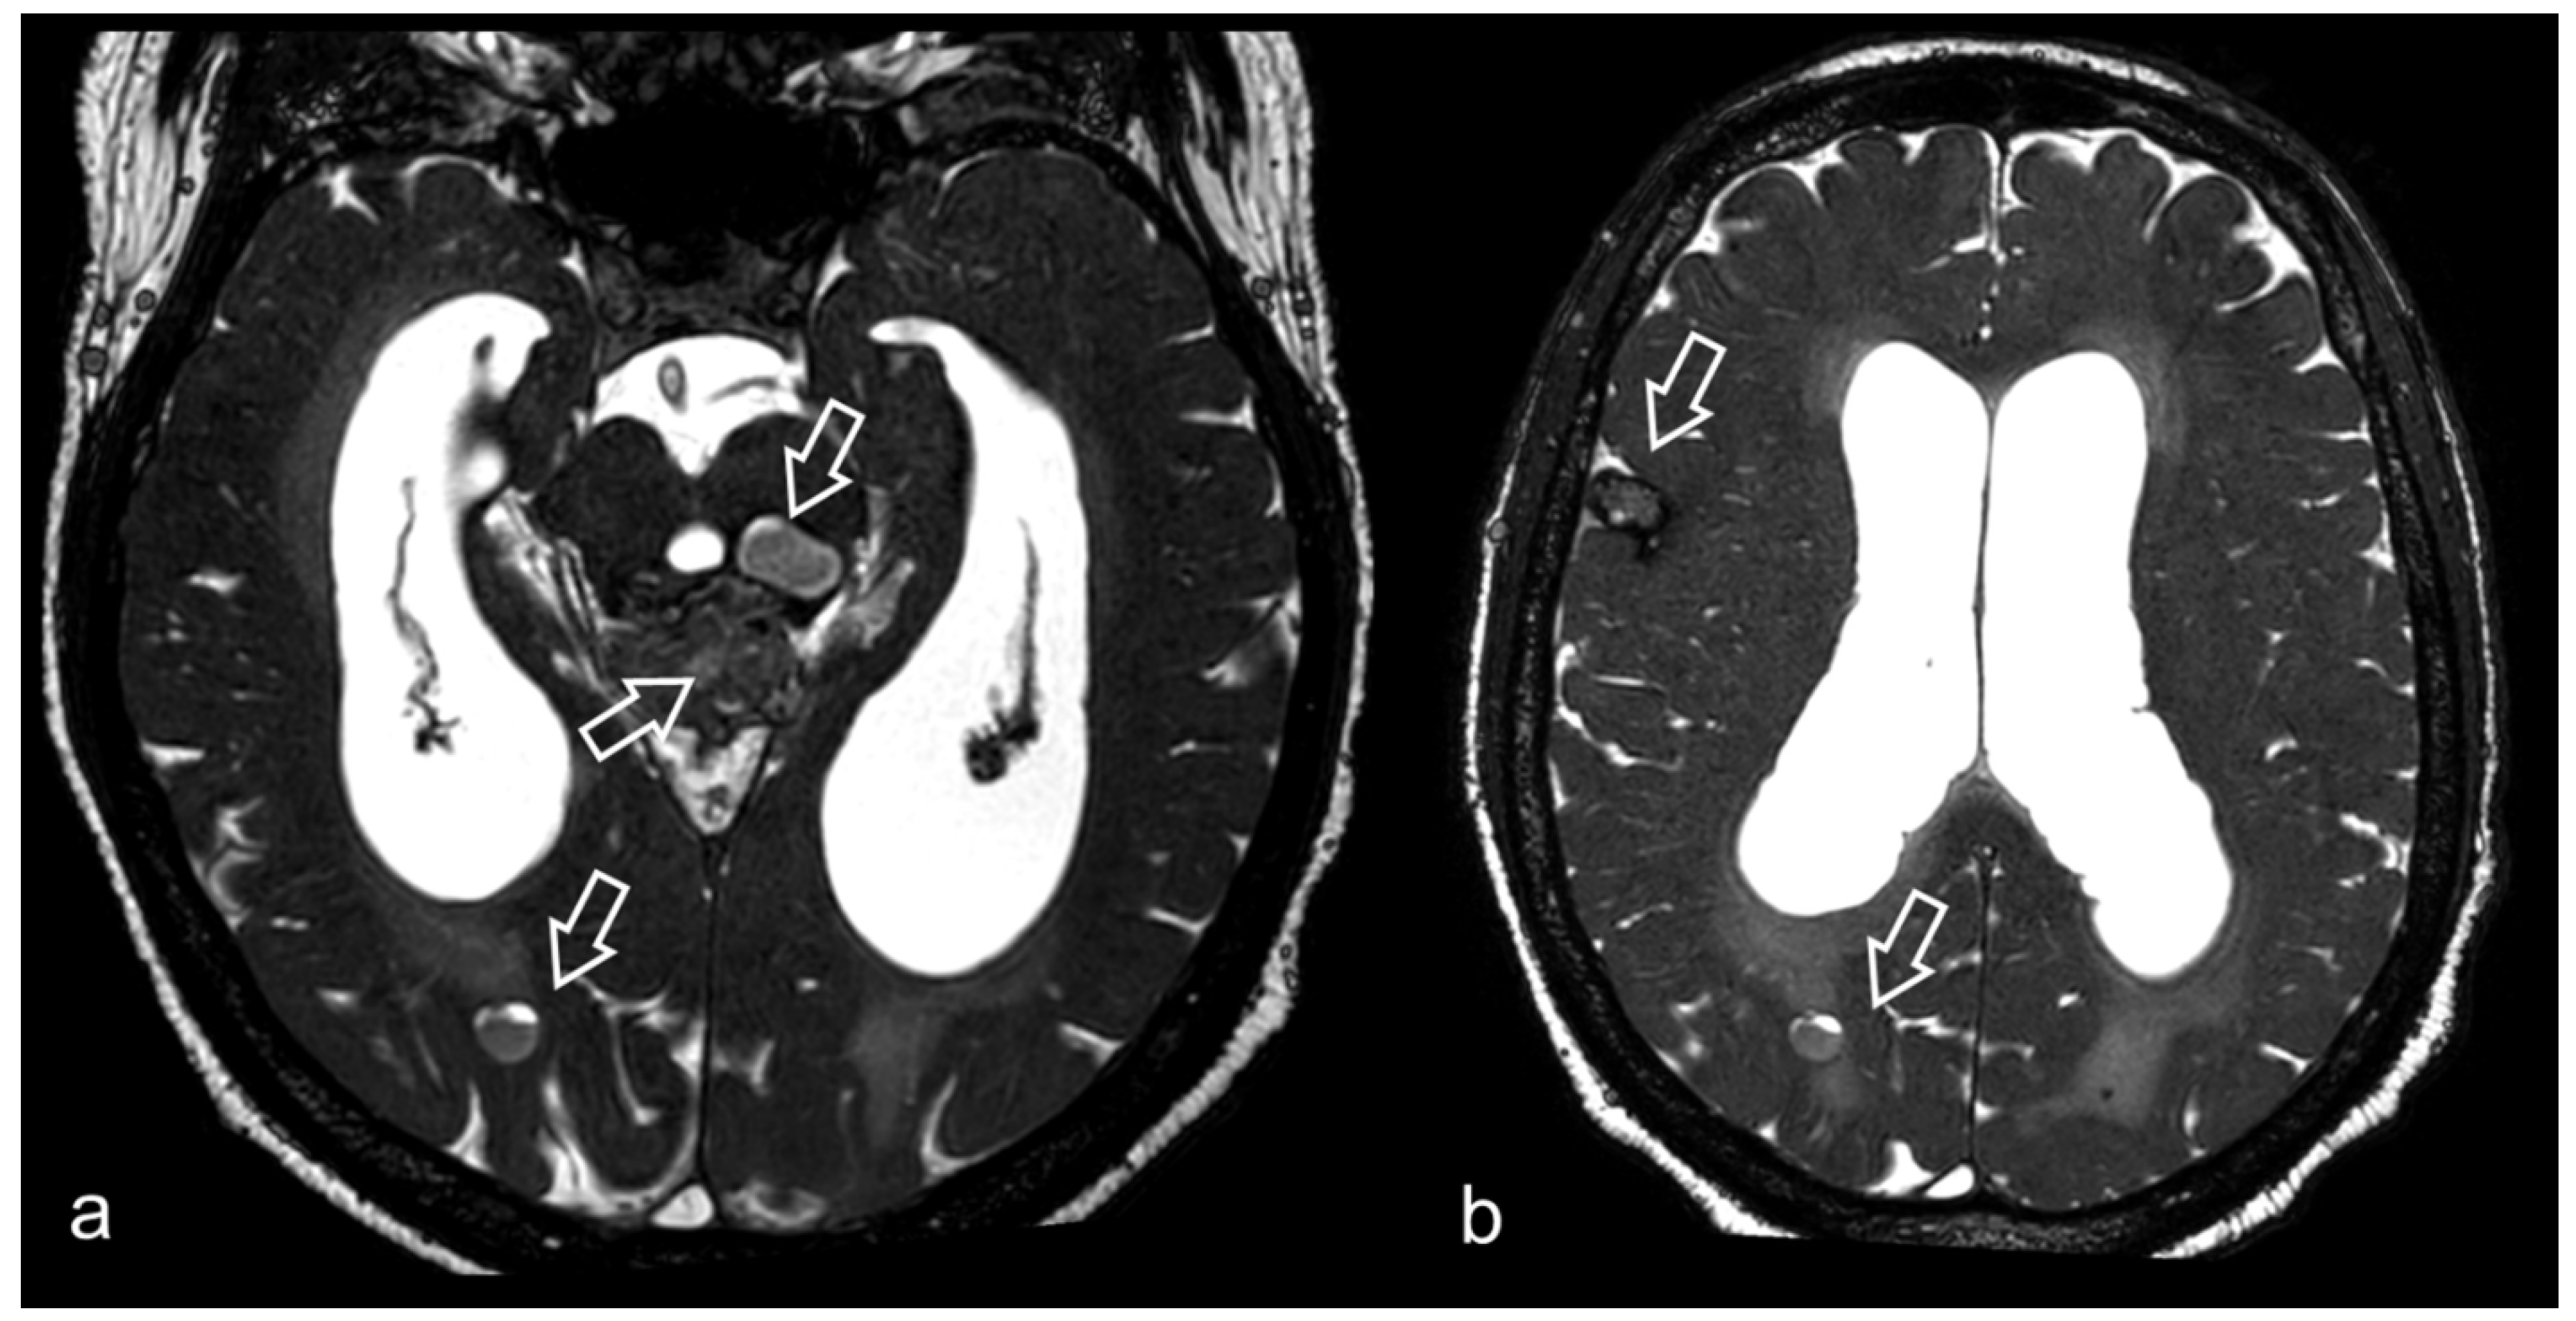

- Kurihara, N.; Takahashi, S.; Tamura, H.; Higano, S.; Furuta, S.; Jokura, H.; Umetsu, A. Investigation of hydrocephalus with three-dimensional constructive interference in steady state MRI. Neuroradiology 2000, 42, 634–638. [Google Scholar] [CrossRef]

- Algin, O.; Hakyemez, B.; Parlak, M. Phase-contrast MRI and 3D-CISS versus contrast-enhanced MR cisternography on the evaluation of the aqueductal stenosis. Neuroradiology 2010, 52, 99–108. [Google Scholar] [CrossRef]

- Shi, J.; Fu, W.; Wu, Q.; Zhang, H.; Zheng, Z.; Zhu, J. Endoscopic third ventriculostomy associated 3D-construcive inference steady state MRI for obstructed hydrocephalus: A retrospective study. Clin. Neurol. Neurosurg. 2013, 115, 896–901. [Google Scholar] [CrossRef] [PubMed]